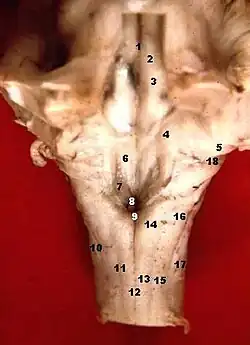

Le « centre du vomissement » est une structure de l'encéphale qui se charge de contrôler les reflux gastriques. C'est un centre afférent et efférent commun, situé dans la moelle allongée à la partie ventrale du tractus solitaire à proximité du centre apneustique et vasomoteur[1].

Il est situé dans une zone assez mal limitée située dans le mésencéphale, dans les stries acoustiques de la fosse rhomboïde, à proximité de l'aire vestibulocochléaire. Il mesure environ 1 mm chez l'humain.